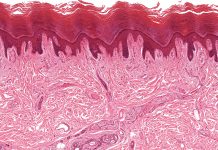

BRoTHER – Can digitalisation improve the interaction of tissue biobanks?

How can digitalisation support interactions between tissue biobanks, and why is this important? The BRoTHER project may have the answers.

The project BRoTHER (Biobank Research...